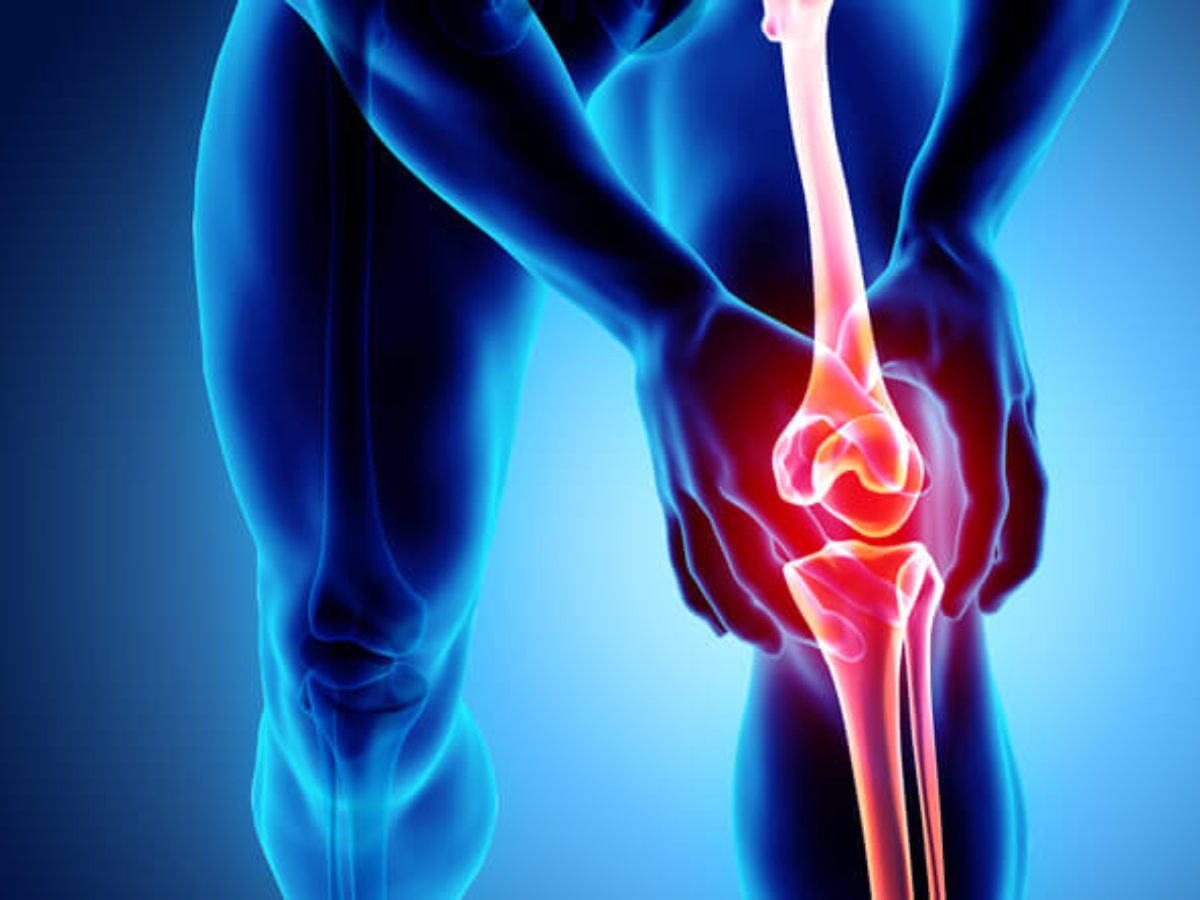

What is the Rotator Cuff? The rotator cuff is a group of muscles and tendons in the shoulder that connect the upper part of the arm (the humerus) to the shoulder blade (scapula). The tendons provide stability to the shoulder joint, while the muscles allow the shoulder to rotate.

- Rotator Cuff Inflammation: This occurs due to irritation and swelling in the shoulder joint.

- Muscle Tears: Muscle tears can occur due to direct injury or the neglect of shoulder muscle strain.

- Ligament Sprains: This can happen due to direct injury or excessive movements.

- Muscle Tears and Strains: The shoulder is susceptible to injuries, including muscle tears and strains in the muscles and tendons. These injuries may occur due to accidents or intense physical activities, causing acute pain and limited shoulder mobility.

- Frozen Shoulder: Frozen shoulder is characterized by pain and stiffness in the shoulders. Several factors, including inflammation of the surrounding tissues or tissue adhesions, can contribute to this condition. Medical intervention and physical therapy are common treatments for frozen shoulder.

- Loss of motion and the ability to use your shoulders: If you have difficulty moving or using your shoulders normally, it could be a sign of a serious problem. This may indicate muscle, ligament, or joint injuries that require immediate attention from a medical professional.